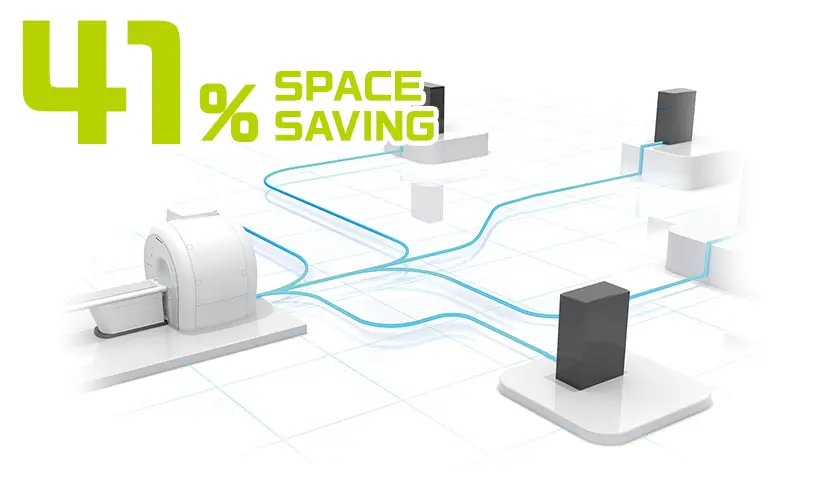

Ekipman odasında süper iletken bir MRG sistemi kurulumu için yeterli alan olup olmadığı genellikle bir endişe konusudur. ECHELON Smart Plus, kurulum sırasında bu tür engelleri ortadan kaldırabilir.